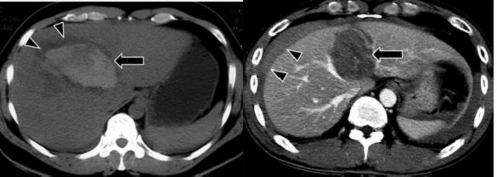

- Máu tụ dưới bao gan: Trên phim chụp CLVT tụ máu dưới bao gan là hình ảnh tổn thương có dạng hình liềm hay thấu kính, nằm giữa bao Glison và nhu mô gan, đè đẩy trực tiếp nhu mô gan lân cận. Tỷ trọng khối máu tụ thay đổi, lúc đầu tăng tỷ trọng tự nhiên, từ 60 – 80 UH, sau đó giảm tỷ trọng dần ở các ngày sau. Sau khi tiêm thuốc cản quang, khối máu tụ không tăng tỷ trọng [19].

Hình 1.7: Tụ máu dưới bao gan có dạng hình liềm (mũi tên dài) hay thấu kính và các khối máu tụ trong nhu mô gan (mũi tên ngắn).

Nguồn: Shanmuganathan K, Mirvis SE [21].